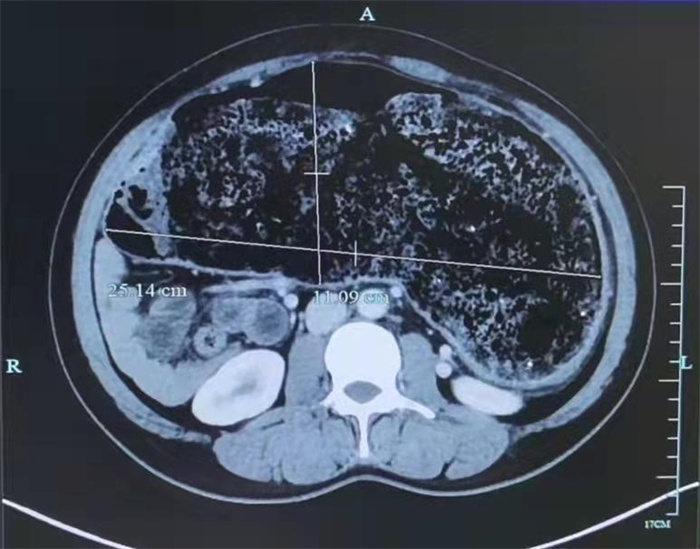

詳細(xì)詢問病史結(jié)合全腹部CT增強(qiáng)檢查,提示何女士乙狀結(jié)腸、降結(jié)腸管腔明顯擴(kuò)大(較寬處管徑約25.14cm),考慮先天性巨結(jié)腸。為徹底解除何女士的困擾,徐天生建議何女士手術(shù)治療。

歷經(jīng)4小時(shí),何女士順利接受了腹腔鏡下全結(jié)腸切除術(shù),取出的結(jié)腸足足比胃還大。